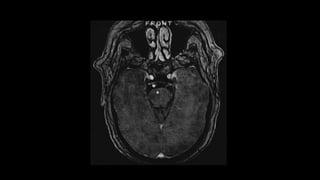

El artefacto en floración es un artefacto de

susceptibilidad encontrado en algunas secuencias de MRI en

presencia de sustancias paramagnéticas que afectan los

ambientes magnéticos locales. Aunque es un artefacto, puede

ser explotado deliberadamente para mejorar la detección de

ciertas lesiones pequeñas, así como los efectos de

acortamiento de T1 de baja concentración de gadolinio se

utilizan para detectar el aumento de contraste .

Una de las secuencias más poderosas y ampliamente

disponibles que maximiza el artefacto en floración con gran

efecto es la imagen ponderada por susceptibilidad (SWI) .

La floración se ve rodeando una serie de compuestos:

•hemosiderina de hemorragia previa, por ej.

• malformaciones cavernosas

• antigua hemorragia intracerebral

• lesión axonal difusa

• siderosis superficial

•calcificación, particularmente distrófica, por ejemplo

• Neurocisticercosis (etapa granulomatosa)

•metal por ejemplo

• Fragmentos quirúrgicos o traumáticos.

•gas por ejemplo

• embolia gaseosa